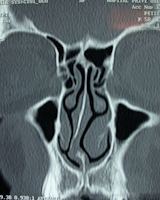

L'étude précise du fonctionnement du nez avant d'envisager une rhinoplastie ou une rhino-septoplastie doit rechercher également une augmentation de volume anormal des cornets inférieurs par simple inflammation chronique ou par rhinite allergique associée. Il y a souvent une hypertrophie du cornet inférieur du côté opposé à la déviation de cloison.

Il faut savoir porter alors l'indication d'une diminution de volume des cornets inférieurs. Il ne se pratique plus de turbinectomie complète accusées d'être à l'origine du syndrome du nez vide, mais plutôt soit une turbinoplastie pour diminution de volume des cornets inférieurs par radiofréquence ou par laser sur fibre souple, celle-ci étant effectuée  dans le même temps que le geste chirurgical. Ce geste associé est simple et rapide et permet de  diminuer le volume excessif de la muqueuse du cornet inférieur en respectant cependant son fonctionnement. Cette intervention sous pratique par voie endoscopique c'est-à-dire en microchirurgie à l'aide d'un système de caméra et d’écran.

Déviations de cloison droite sans

excès de volume du cornet

inférieur gauche